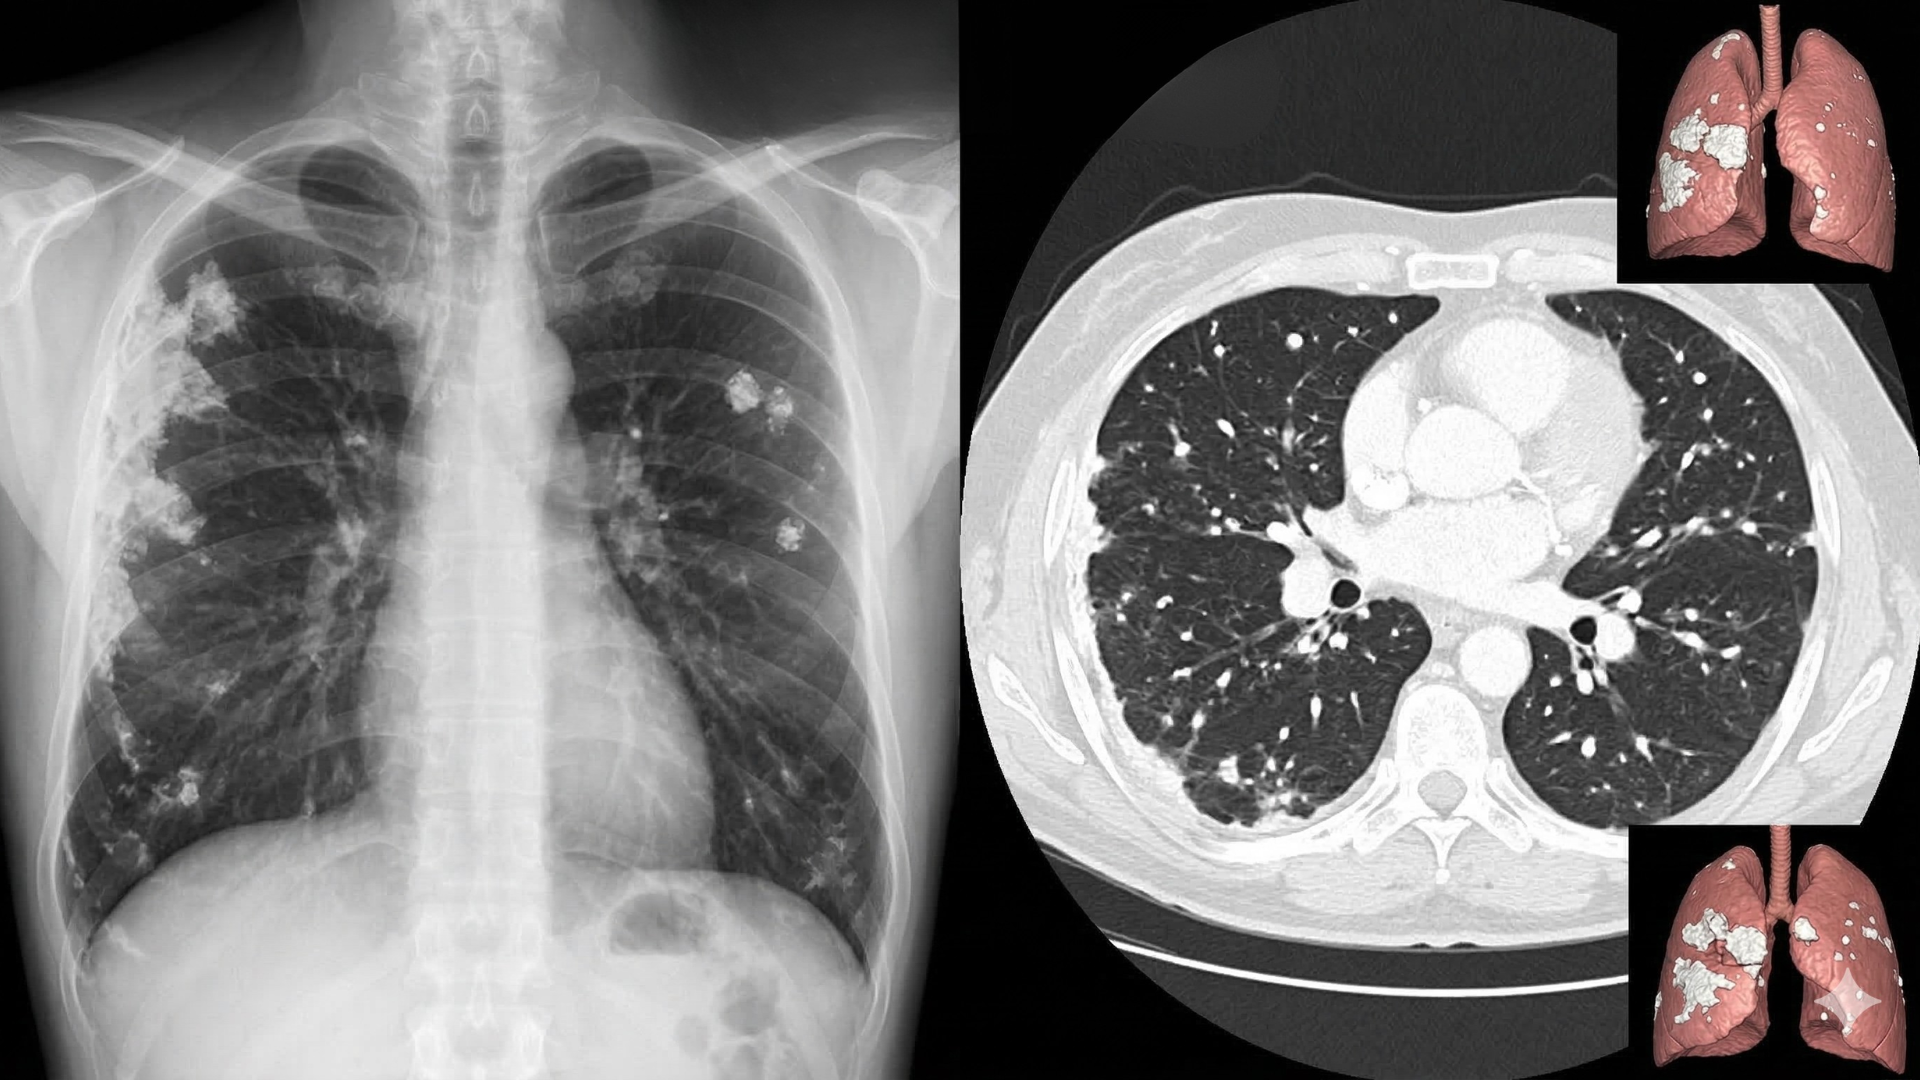

Trong quá trình khám sức khỏe hoặc chụp X quang ngực, một số người có thể được thông báo xuất hiện vôi hóa phổi dưới dạng các nốt sáng nhỏ trong nhu mô phổi. Phần lớn trường hợp là dấu hiệu còn lại sau viêm hoặc nhiễm trùng trước đó, nhưng việc hiểu rõ vôi hóa phổi vẫn giúp theo dõi sức khỏe hô hấp tốt hơn.

Vôi hoá phổi là hiện tượng muối canxi lắng đọng trong các mô phổi hoặc trong các nốt nhỏ hình thành ở nhu mô phổi. Những nốt này thường xuất hiện dưới dạng đốm sáng trên hình ảnh chẩn đoán như X quang hoặc chụp cắt lớp vi tính.

- Chụp X quang phổi.

- Chụp CT ngực.

Những phương pháp này giúp xác định cấu trúc và đặc điểm của nốt phổi.